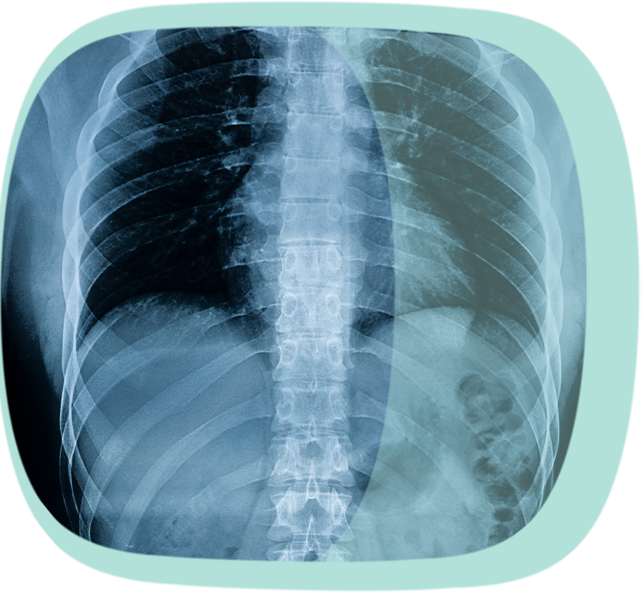

Damit die Diagnose einer axialen Spondyloarthritis gestellt werden kann, ist zunächst ein ausführliches ärztliches Gespräch notwendig, um die Beschwerden sowie die Krankengeschichte des Patienten und die Krankengeschichte der Angehörigen zu erfassen. Erhärtet sich der Verdacht auf eine axiale Spondyloarthritis, werden weitere Untersuchungen veranlasst, um bei Vorliegen von typischen Beschwerden die Diagnose einer axialen Spondyloarthritis zu stellen. Dazu zählen Röntgenaufnahmen des Beckens und der Wirbelsäule, Magnetresonanz-Untersuchungen der Kreuzdarmbeingelenke und eventuell von schmerzhaften Stellen an der Wirbelsäule und den Gliedmaßen sowie Laboruntersuchungen zum Nachweis von Entzündungsmarkern und des HLA-B27 Gens. Auch mikrobiologische, molekularbiologische und serologische Untersuchungen zur Entdeckung einer zuvor abgelaufenen Infektion des Darmes oder des Genitales sind manchmal erforderlich.

Ein Röntgenbild eines Brustkorbes

iStock-1203743434_Melena-Nsk